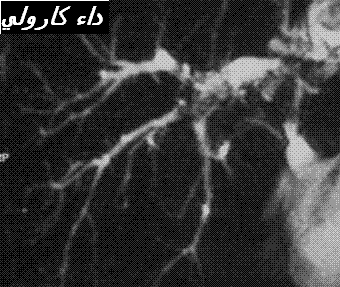

1 – التوسع الأصلي الجيني للقنوات الصفراوية داخل الكبد (20) ( كثيرا ما تمسي مصحوبة بتوسيع القناة الصفراوية الرئيسية) . و تعتقد هاته الحالة شائعة نسبيا في البلدان الأسيوية و استثنائية في الغرب تحت شكل داء كرولي (21)

Maladie de Caroli

قد يبو صعبا علاج الحصى داخل الكبد خاصة في حالة الانتشار المتسرب للحصى المصحوب باضطرابات متعددة للمسالك الصفراوية . و قد يتطلب العلاج تدخل عدة اختصاصات. و يحتمل في هاته الحالة للحصى الكبير الحجم البني اللون الكبير الحجم ، يحتمل اقتراح العلاج بعقار الأورسوديزوكسيكولك بالرغم من قلة الحجج المتوفرة . و الحقيقة فان وجود الكوليستيرول في هذا الصنف من الحصى يرفع من فعالية الدواء أثناء الاصابة بداء كرولي (40) .